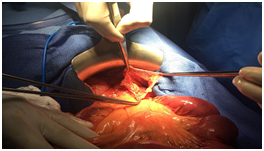

All the patients were explored urgently by midline incisions. The different types of hernia found were through: Paranormal orifice: 3 left paraduodenal (Figures 2) (Figure 3A) (Figure 3B), 2 right paraduodenal, 1 intra-mesosigmoidal and 1 retrocecal. Abnormal pathologic orifice: 2 trans-mesenteric (Figures 4A-4C), 1 in the posterior cavity through a colo-omental dissinsertion hole Figure 5 and 1 trans-omental. The Reduction of the herniated viscera was never a problem but a bowel necrosis was found in two cases, which required dilatation of the hernial orifice and resection of 1, 25m and 60cm of small bowel with immediate restoration of continuity. The closure of peritoneal fossae or an abnormal orifice was done easily with a resorbable suture (Table 2). We had no death in our patients. Two cases of wound infection were reported classified Grade I in the Clavien-Dindo classification of surgical complications. These patients were treated by antibiotics and had local treatment. The length of hospital stay was 8 days (3-11days). In the follow-up, there was no recurrence.

Figure 4A Tran’s mesenteric hernia with bowel necrosis.

Figure 4B The trans mesenteric orifice and the bowel reduced from it.

Figure 4C Closure of a trans mesenteric hernia’s orifice, after the resection of bowel necrosis and immediate restoration of continuity.